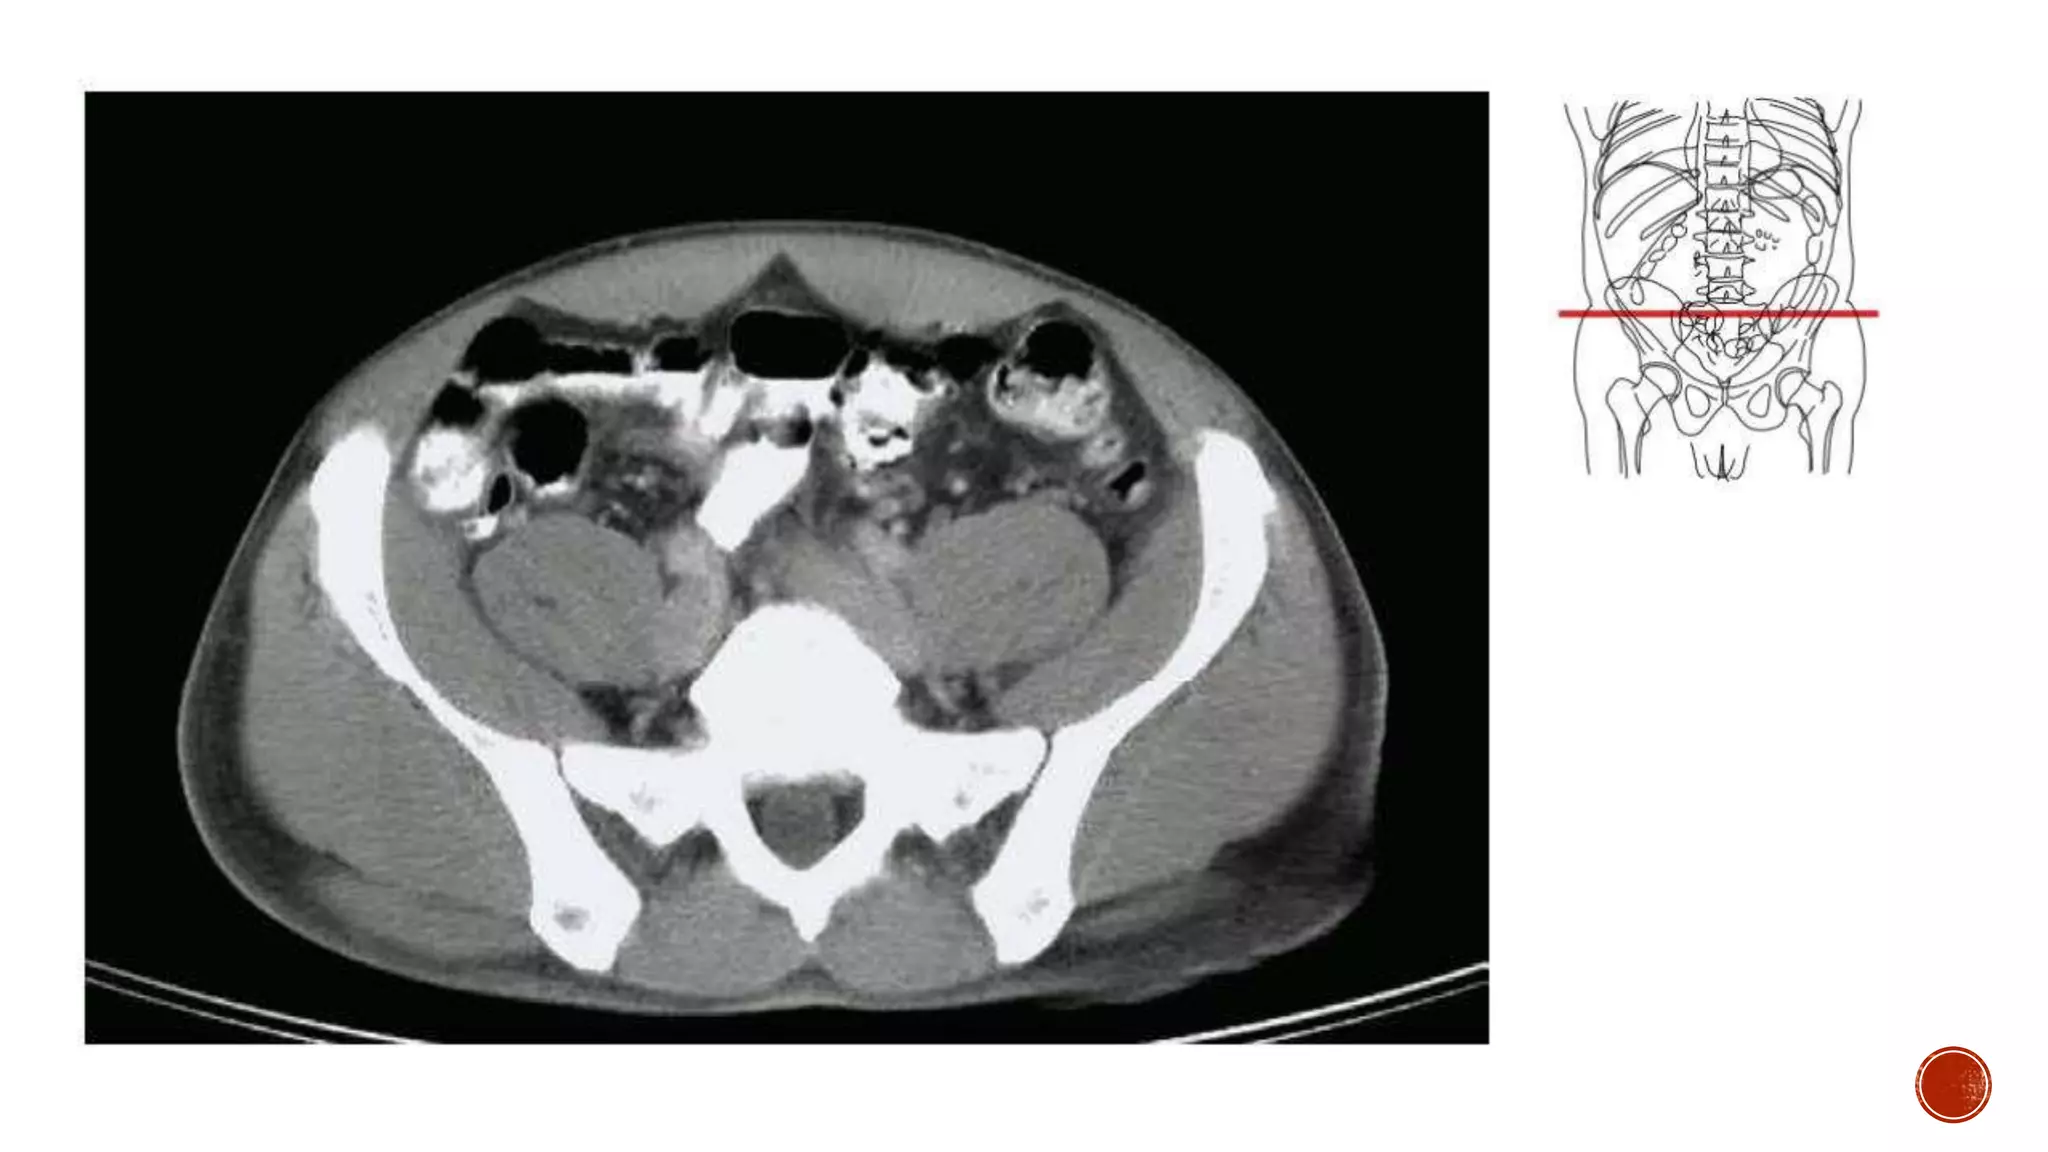

The document describes the anatomy of the abdomen and pelvis region of the human body. It lists over 40 structures and their locations, including major organs like the liver, kidneys, intestines, blood vessels and muscles of the abdominal wall and pelvis. The structures are grouped into sections focusing on different anatomical areas like the abdomen, retroperitoneum, pelvis and gluteal region.